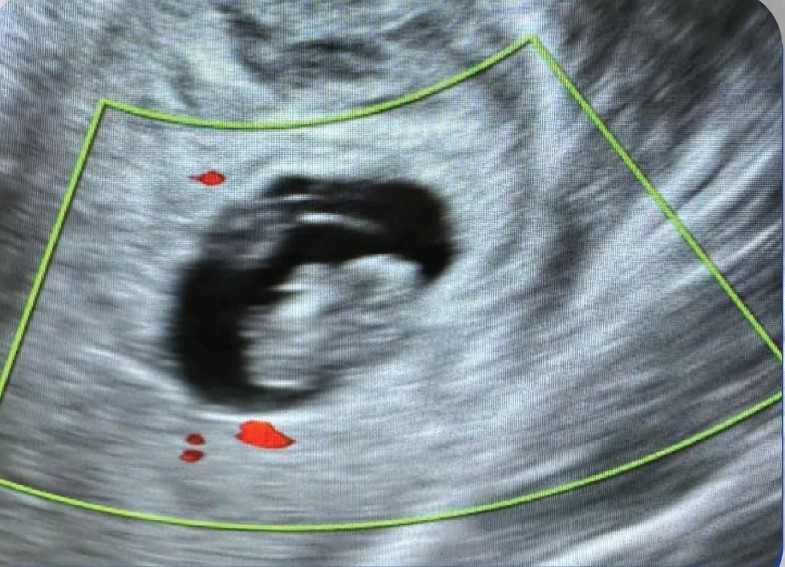

Kết quả siêu âm vỡ khối chửa ngoài tử cung - Ảnh BVCC

Qua thăm khám ban đầu, các bác sĩ Khoa Phụ sản – Bệnh viện Hữu nghị Lạc Việt ghi nhận bệnh nhân có dấu hiệu thiếu máu nặng, da xanh, niêm mạc nhợt, choáng, bụng chướng và có phản ứng thành bụng. Ngay lập tức, bệnh nhân được chỉ định siêu âm khẩn cấp.

Kết quả cho thấy túi thai ngoài tử cung bên phải, tương đương khoảng 8 tuần tuổi, không có tim thai và ổ bụng có nhiều dịch máu.

Bệnh nhân được chẩn đoán vỡ khối chửa ngoài tử cung, tình trạng đe dọa trực tiếp đến tính mạng. Các bác sĩ đã nhanh chóng chỉ định phẫu thuật cấp cứu để xử trí và cầm máu. Do bệnh nhân mất máu nhiều trước đó, trong quá trình phẫu thuật, ê-kíp đã truyền 2 đơn vị máu nhằm đảm bảo an toàn.